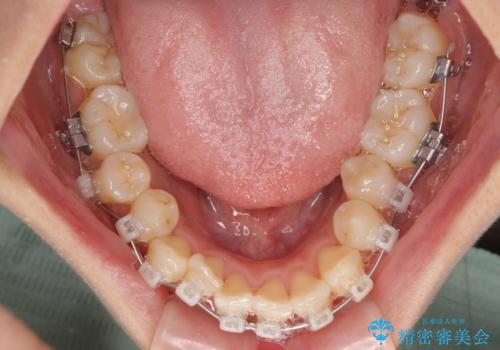

- クリアブラケット

- 治療期間

- 1年3ヶ月

- 上下前歯のデコボコを気にして来院された患者様です。

上顎歯列が下顎の歯列に対して狭小であり、一部下顎の奥歯が上顎よりも外側に位置している状態でした。

上顎の急速拡大装置を使用して上顎骨を側方に拡大することで上顎歯列を拡大し、下顎歯列も拡大できるようにすることで、歯列を整えることとしました。